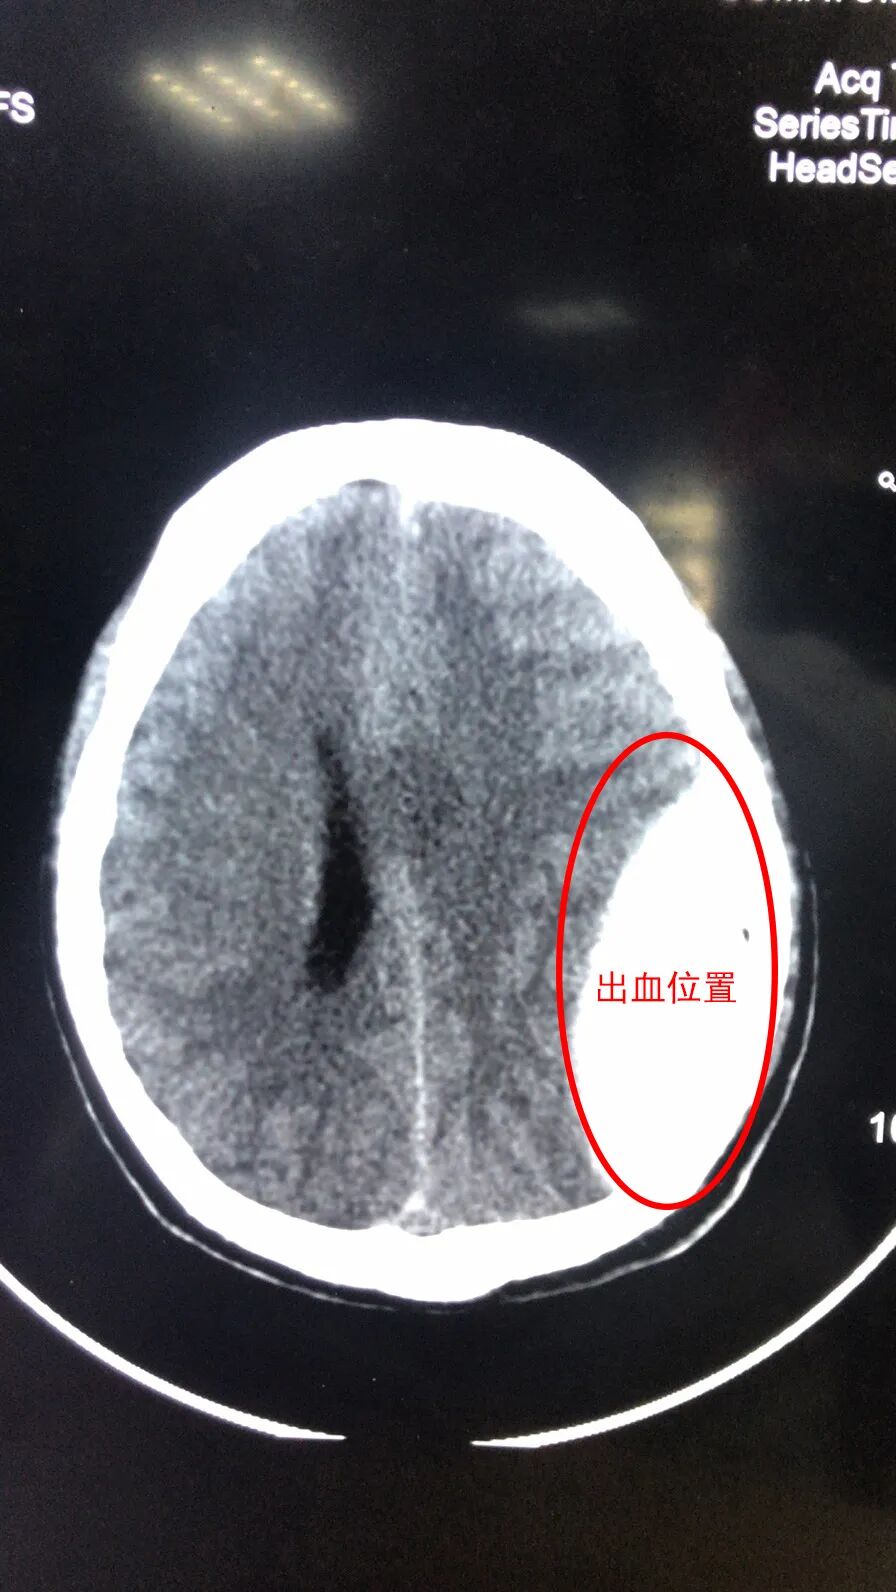

经过CT检查,陈师傅顶部硬膜外血肿,顶骨骨折,同时左侧多处肋骨骨折,情况危急,急症检查完后就立刻转入ICU救治。经过ICU和神经外科联合救治,陈师傅目前已经恢复了意识,是否已经脱离危险,还需要进一步观察。

手术后